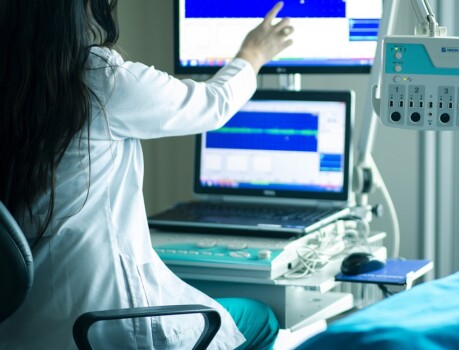

Atención Integral Medica Especializada con ética y de alta calidad en todas las etapas de la vida de la mujer es nuestro compromiso, con un abordaje amplio en consultas y manejos que comprenden desde la revisión preventiva, el diagnóstico oportuno con opciones avanzadas y tratamiento de las condiciones ginecológicas y obstétricas.

Diferentes opciones de diagnóstico son ofrecidas para identificar problemas potenciales del feto y de la madre con acceso a un equipo multidisciplinario para el mejor cuidado en las diferentes etapas.

Con tecnologías y evidencias medicas para el diagnostico y tratamiento de las enfermedades que afectan a la mujer.